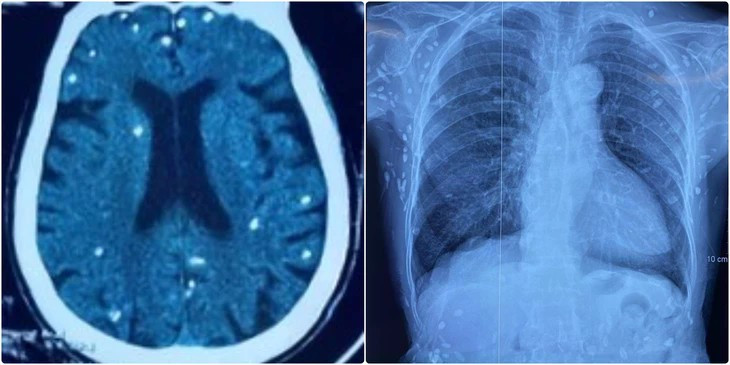

Người bệnh được chuyển lên từ tuyến dưới vì rối loạn ý thức, đe dọa suy hô hấp, hình ảnh cắt lớp vi tính sọ não và X-quang ngực cho thấy rất nhiều nốt cản quang trong nhu mô não và dưới da vùng ngực-bụng.

Theo bác sĩ Nguyễn Thị Vân Anh, khoa hồi sức truyền nhiễm, Bệnh viện Trung ương Quân đội 108, mặc dù xét nghiệm kháng thể IgM với sán dây lợn âm tính, các tổn thương trên X-quang gợi ý người bệnh trước đây bị nhiễm ấu trùng sán dây lợn, sau đó các nang sán trở nên vôi hóa và tồn tại lâu dài trong cơ thể.

Nang sán dây lợn có thể tự thoái hóa hoặc bị vôi hóa, tạo nên nhiều hình ảnh cản quang phát hiện được trên phim X-quang như trường hợp bệnh nhân trên.